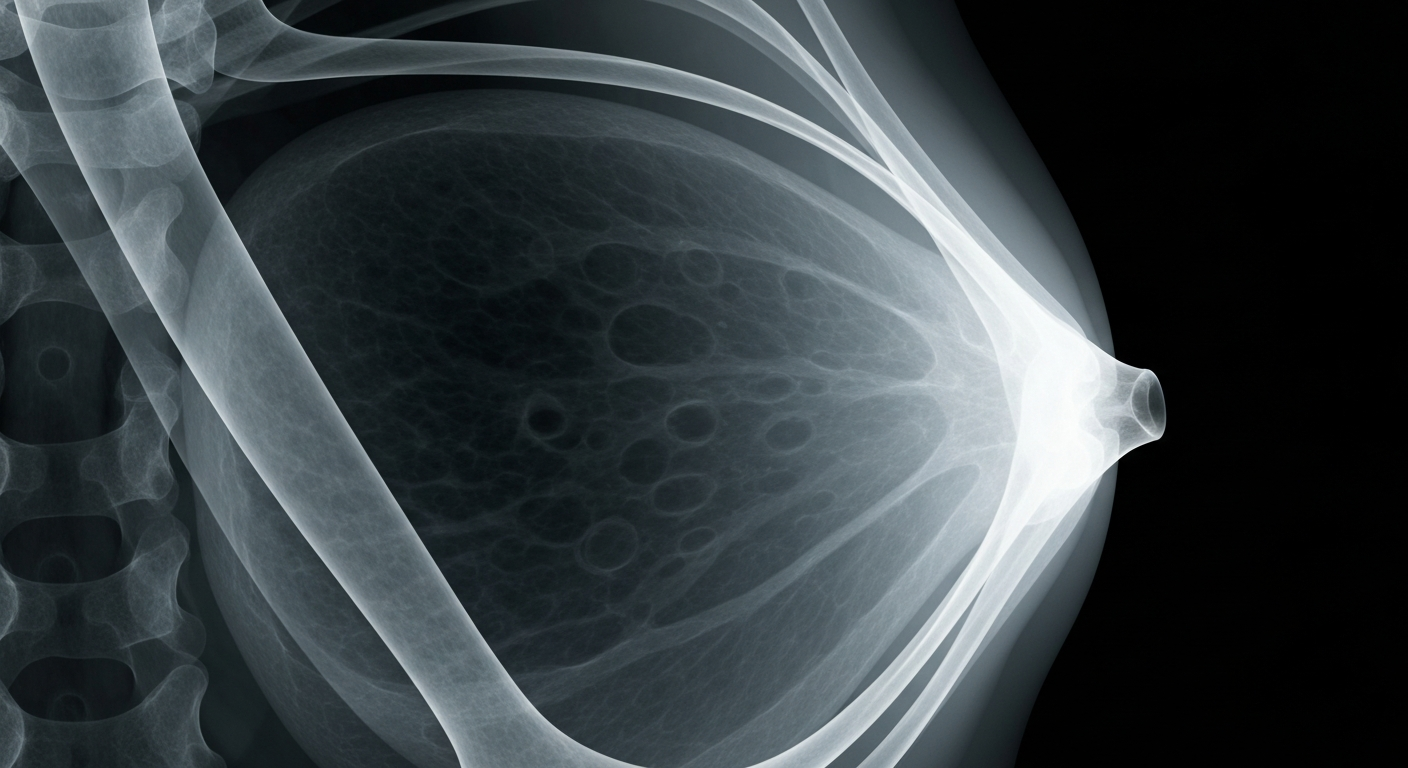

ACP Updates Breast Cancer Screening Guidance

New recommendations support biennial screening for women aged 50-74, with individualized decisions for younger and older women.

New breast cancer screening guidelines aim to balance the benefits and harms of mammography, especially for women with dense breast tissue.Boston TodayThe American College of Physicians (ACP) has updated its guidance on breast cancer screening for asymptomatic, average-risk women. The new recommendations include biennial mammography for those aged 50-74, shared decision-making for women 40-49 and those 75+, and advice against supplemental MRI or ultrasound for women with dense breasts.

The updated ACP guidance aims to balance the benefits and harms of breast cancer screening, addressing concerns around overdiagnosis, overtreatment, and false positives that can lead to unnecessary stress and reduced adherence to future screening.

The key recommendations include: 1) Biennial mammography for women aged 50-74, 2) Shared decision-making for women 40-49 and those 75+, considering individual risk and preferences, 3) No recommendation for supplemental MRI or ultrasound for women with dense breasts, and 4) Continued advice against routine breast self-exams.